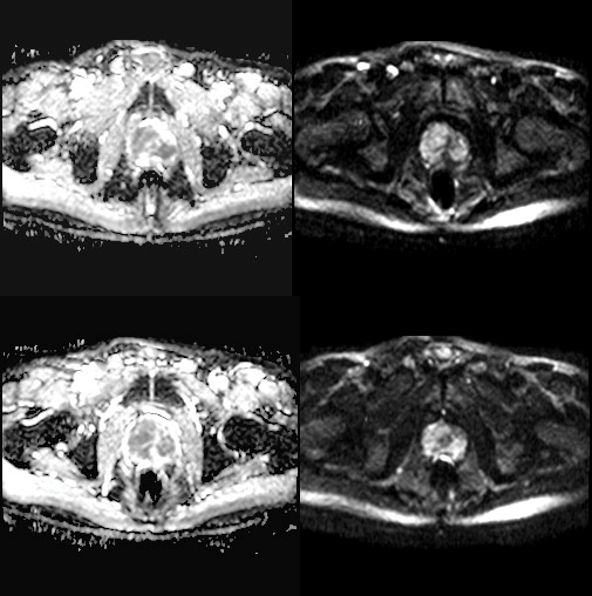

MR

2018.6影像表现如下:

前列腺外周带及中央腺体异常信号灶,前列腺癌待排,累及右侧精囊腺。盆腔及两侧腹股沟肿大淋巴结。